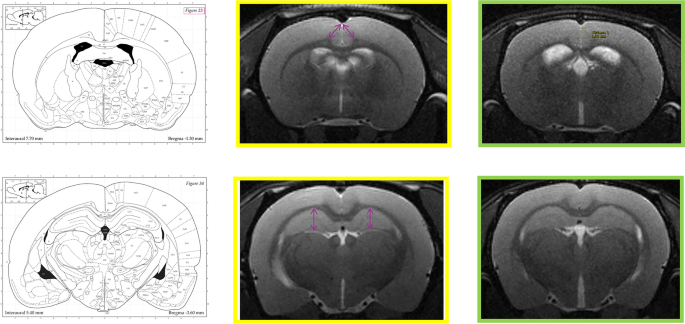

Differences were also observed in ventricular size, as well as in the shape and thickness of the PFC (Fig. 2). Specifically, the thickness of the cingulate cortex (averaged between hemispheres) at –1.30 mm from bregma was significantly reduced in the WKY/CMS rats (1.39 ± 0.07 mm) compared to W/CTRL (1.49 ± 0.06 mm; p = 0.003). Similarly, the average Hip thickness at –3.60 mm from bregma was lower in WKY/CMS rats (1.82 ± 0.03 mm) than in W/CTRL (1.90 ± 0.05 mm; p < 0.01).

Thickness of cingulate cortex and Hip in W/CTRL (yellow) vs. WKY/CMS (green) by using high resolution T2W MRI (TR/TE = 3463/33 ms, matrix 192 × 192, FOV = 25 × 25mm2, thickness = 0.6 mm, 1 average, axial orientation). Upper row: cingulate cortex; lower row Hip. The purple double-headed arrows denote the regions where thickness was measured.